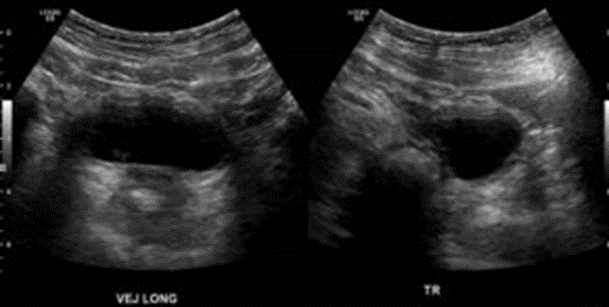

• Antecedente clínico Procedimiento Mitrofanoff o Apendicovesicostomia​

• En relación con cara superior de la Veiga, conexión hacia región umbilical mediante tejido intestinal (apéndice), con capas intestinales claramente diferenciadas. Conducto se visualiza permeable a sonda para drenaje vesical.​

• Vejiga distendida, contenido anecogénico homogéneo.​

• Leve engrosamiento de la pared vesical anterior​

Hallazgos: Vejiga en repleción, de paredes engrosadas en forma difusa, mide 4 mm.

Destaca drenaje vesical umbilical , a través de apéndicovesicostomía, según antecedentes clínicos.

Volumen premiccional 179 cc .